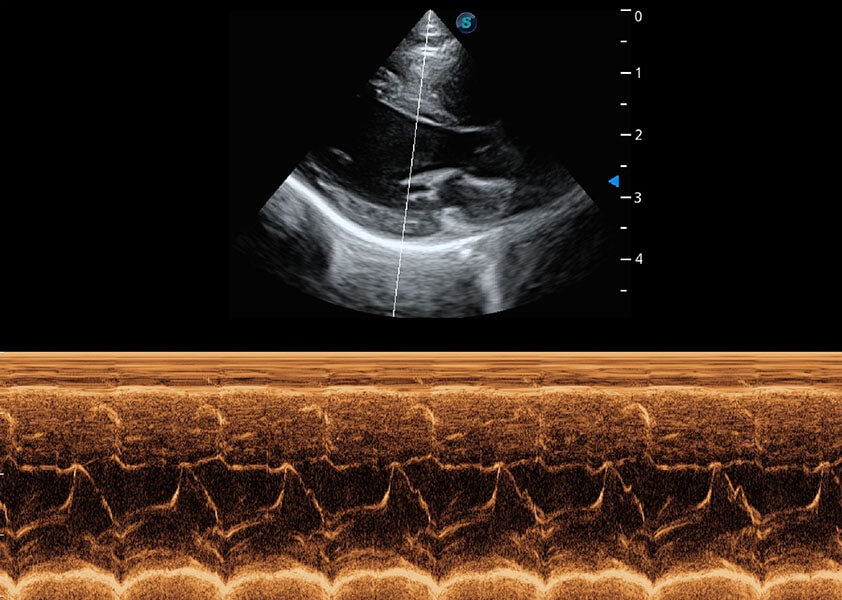

ProPet 60 作為一款高端臺式動物超聲設(shè)備,為動物醫(yī)生的日常診斷提供了一系列貼合動物臨床需求、解決臨床實際問題的高級成像功能。憑借全系列高清探頭,滿足醫(yī)生對腹部、心臟、生殖、淺表、肌骨等成像的所有需求,切實幫助您提升檢查效率,提高診斷信心。